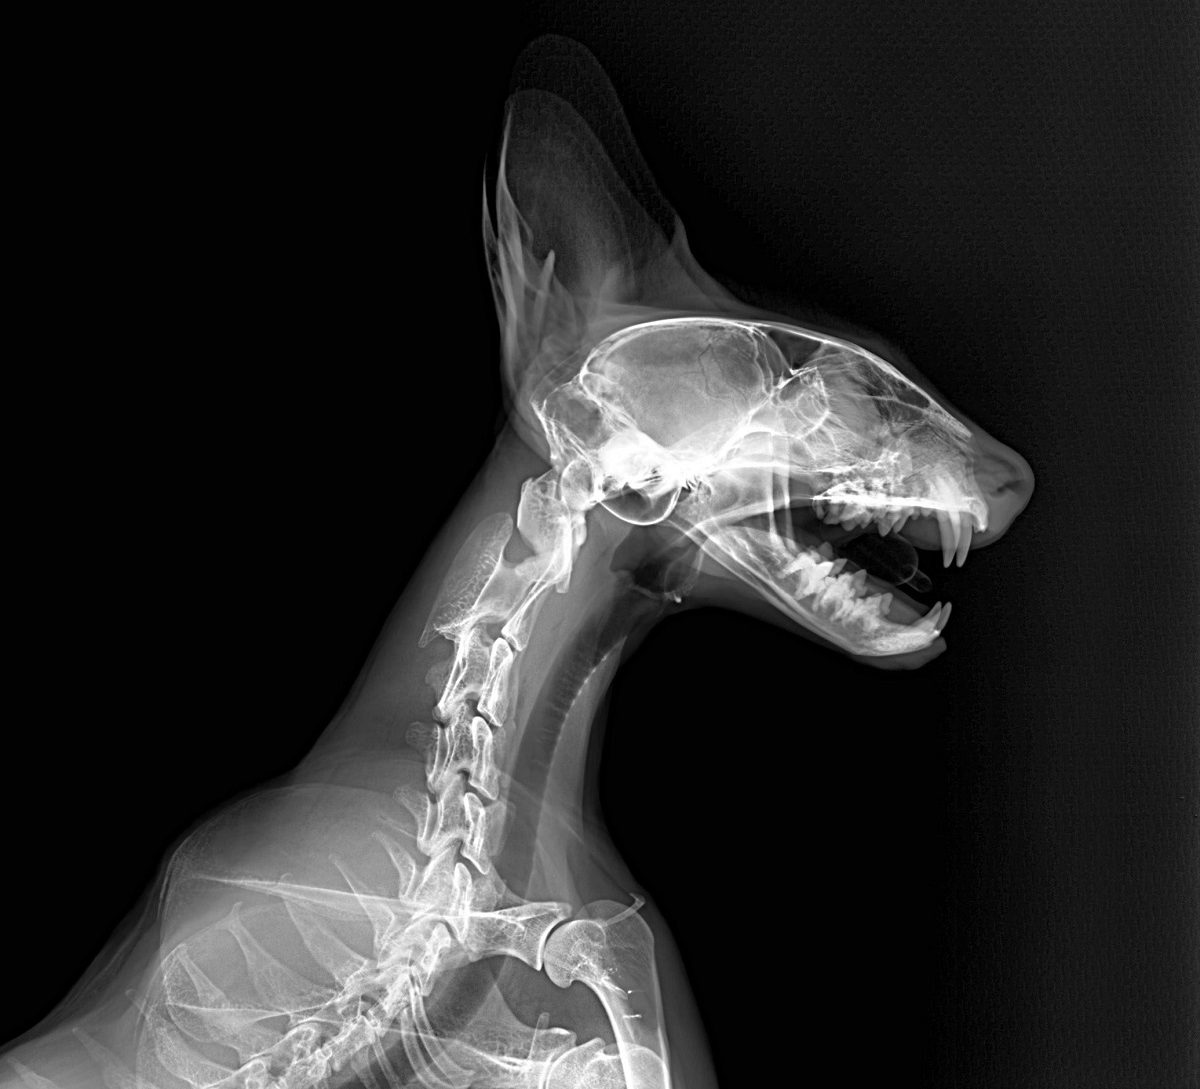

Cada uno de los animales que alberga Bioparc Fuengirola recibe numerosas atenciones que garantizan su bienestar y aseguran que su estado de salud sea el correcto. Entre estos trabajos, se encuentran los seguimientos médicos que realiza el equipo de Veterinaria del parque. Unos controles que, por supuesto, incluyen radiografías.

Este procedimiento diagnóstico permite a nuestros expertos brindar una excelente atención médica. Al exponerlos a los rayos X, el equipo puede tomar fotografías de las partes óseas internas de los animales, comprobando la existencia de lesiones o enfermedades que a simple vista no podrían ser identificadas.

Pero, ¿cómo se toma una radiografía de un tigre de Sumatra, de un cálao Gorginegro, un flamenco o un encantador armadillo de tres bandas?

Como indica Rosa Martínez, veterinaria en Bioparc Fuengirola, “los animales considerados peligrosos para su manejo requieren de un proceso de anestesia previo a la toma de radiografías. Por ejemplo, un tigre de Sumatra no va a prestarse voluntariamente para realizar el estudio. Es necesaria una inmovilización previa, normalmente con anestesia general, para realizar estas pruebas diagnósticas, esenciales para asegurarnos que todo está bien”.